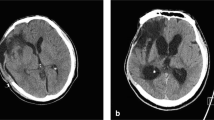

The diagnosis of PTH was based on the compliance of clinical symptoms with radiological images. Several clinical circumstances such as the decrease in the level of consciousness, persistent headache, nausea, vomiting, papilledema, focal neurologic deficits, and cognitive changes (decreased memory, decreased attention, and irritability) were considered to establish the diagnosis of PTH. While deciding if VPS should be performed, the definition of radiological PTH was established in reference to previous studies [9, 10]. The following were accepted as PTH criteria: radiologically determined lateral ventricular dilatation with an Evan’s Index of ≥ 30%, periventricular lucencies marked around frontal and occipital horns, decrease in intersulcal spaces at the convexity, and expansion of the third ventricle.

The maximum width of subdural hematoma, midline shift before DC, presence of contusion, status of basal cisterns, presence of subarachnoid hemorrhage (SAH), and presence of skull fractures were compared between the two groups. Midline shift was described as the length of the displacement of the septum pellucidum from the midline [25]. The basal cistern status was categorized as normal, compressed, or absent [37].

Demographic, clinical, radiological, operative, and postoperative data of all patients are summarized in Table 1. There were no significant differences in age, sex, medical history (hypertension and diabetes mellitus), mechanism of trauma, GCS scores before DC, affected cerebral hemisphere side, pupil size, maximum width of subdural hematoma, midline shift, presence of contusion, presence of cranial fracture, the status of basal cisterns, presence of SAH, the time interval between the trauma and DC, duraplasty and cranioplasty material, and incidence of meningitis between the two groups (Tables 1, 2).